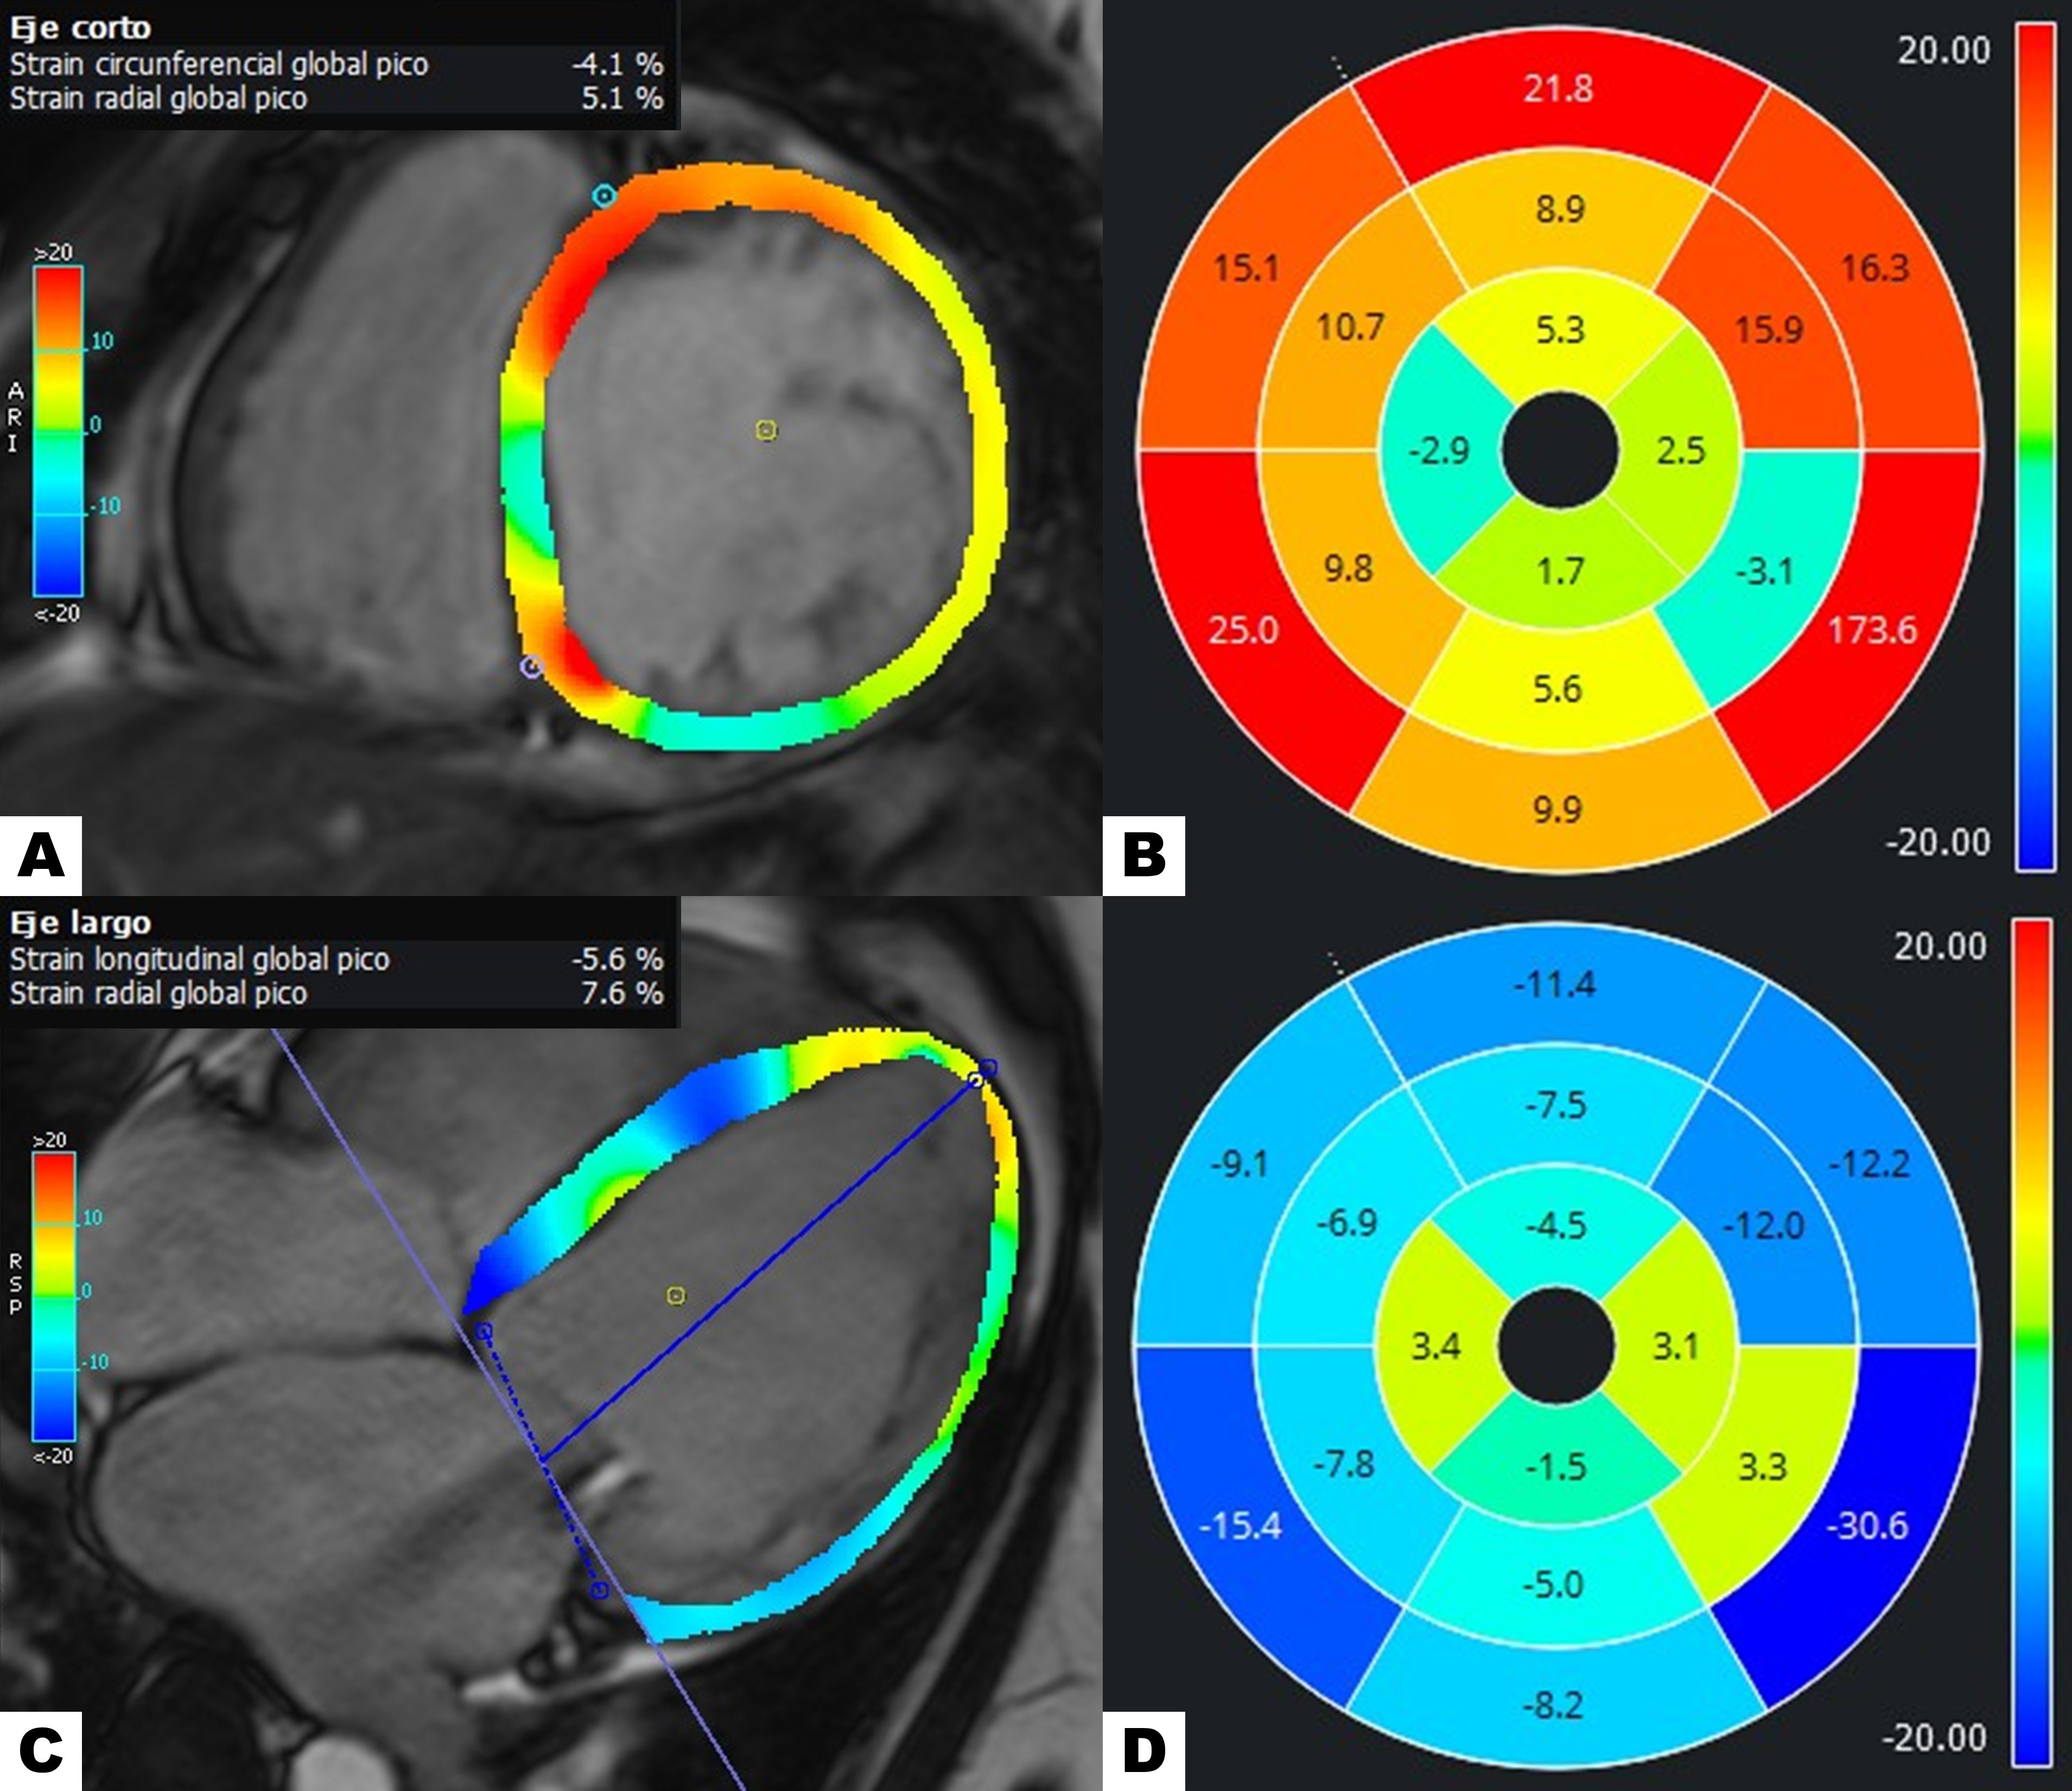

Diagnostic Techniques and Their Most Important Findings: Cardiac Magnetic Resonance (Fig 2-3):

- Left ventricular systolic dysfunction: LVEF 17%, global longitudinal strain −5.6%, global circumferential strain −4.1%.

Figure 2. Cardiac magnetic resonance. (A) Balanced steady-state free precession cine short-axis view. (B) Elevated native T1 mapping values in the lateral wall across all three segments (1,124 ms). (C) Post-contrast T1 mapping showing an extracellular volume of 38%. (D) T2 mapping within the normal range. (E) T2* mapping within the normal range. (F) Short-axis first-pass perfusion demonstrating normal myocardial perfusion. Phase-sensitive inversion-recovery sequence showing LGE with transmural enhancement in the anterior, lateral, and inferior walls: (G) Four-chamber view, (H) Short-axis view. Figure 3. Myocardial strain evaluation with feature tracking technique. (A–B) Circumferential strain. (C–D) Longitudinal strain.

Figure 3. Myocardial strain evaluation with feature tracking technique. (A–B) Circumferential strain. (C–D) Longitudinal strain.